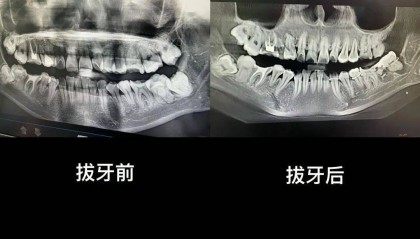

“痛到崩溃”!市卫健委回应“女子在医院跳楼”

近日,安徽一名女子在网络自述“被安庆市立医院口腔科医生拔错牙齿并错误塞回”,后将个人简介改为“在市立...